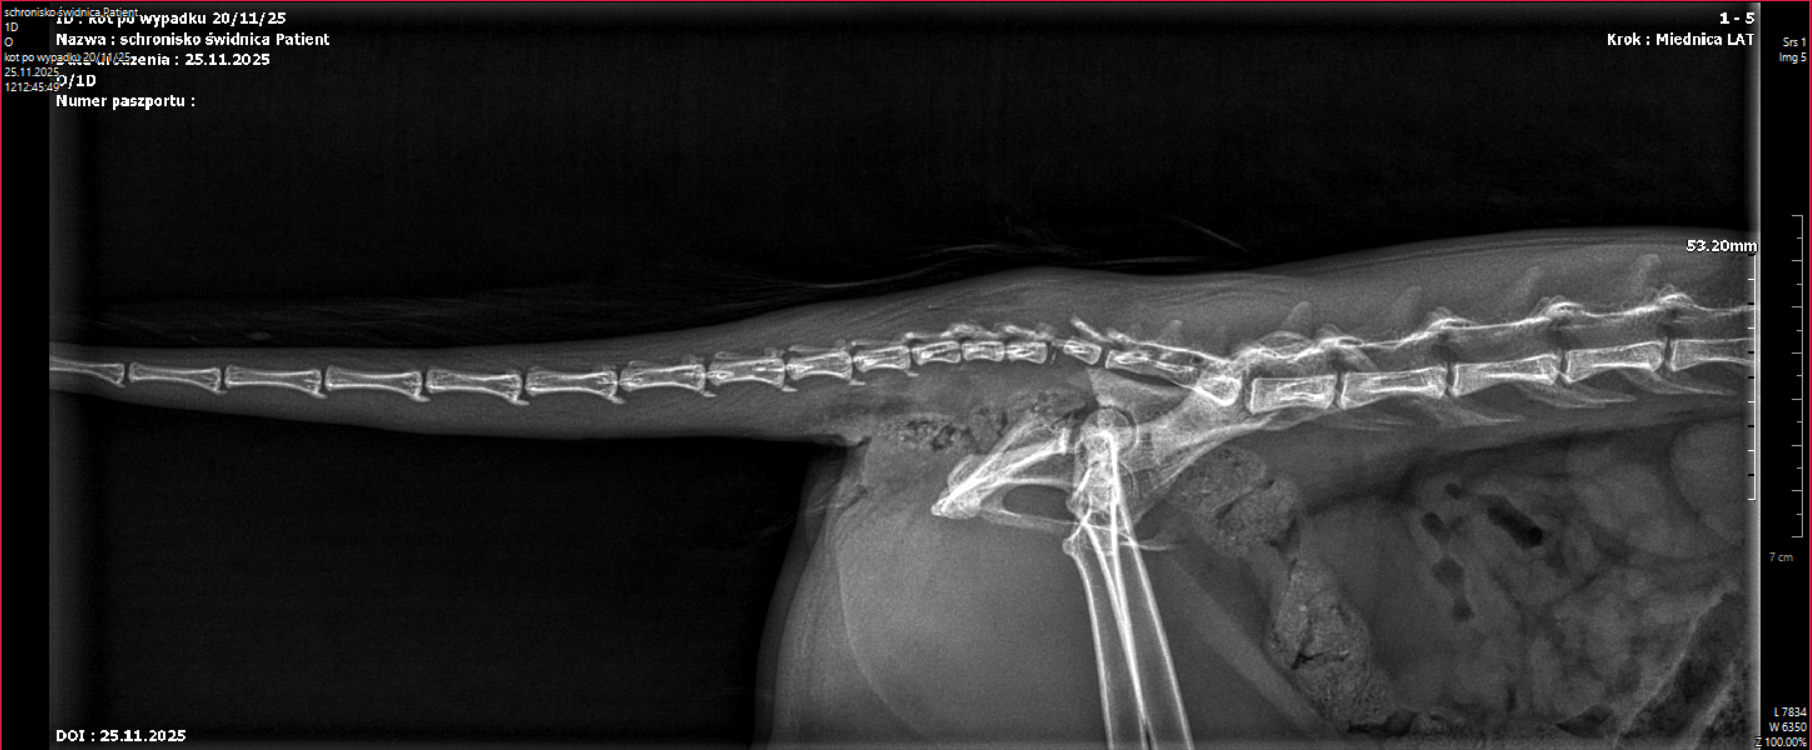

– Coco w stanie silnego bólu trafiła natychmiast do weterynarza. Po wykonaniu badań RTG i pełnej diagnostyki okazało się, że jej obrażenia są poważne i rozległe. Stwierdzono m.in.: obustronne zwichnięcie stawów biodrowo-krzyżowych, złamanie panewki prawego stawu biodrowego, rozejście się nieprawidłowo zrośniętego starego złamania z przemieszczeniem kości kulszowej, zerwanie ogona (uraz kręgosłupa ogonowego) – opisują pracownicy placówki.